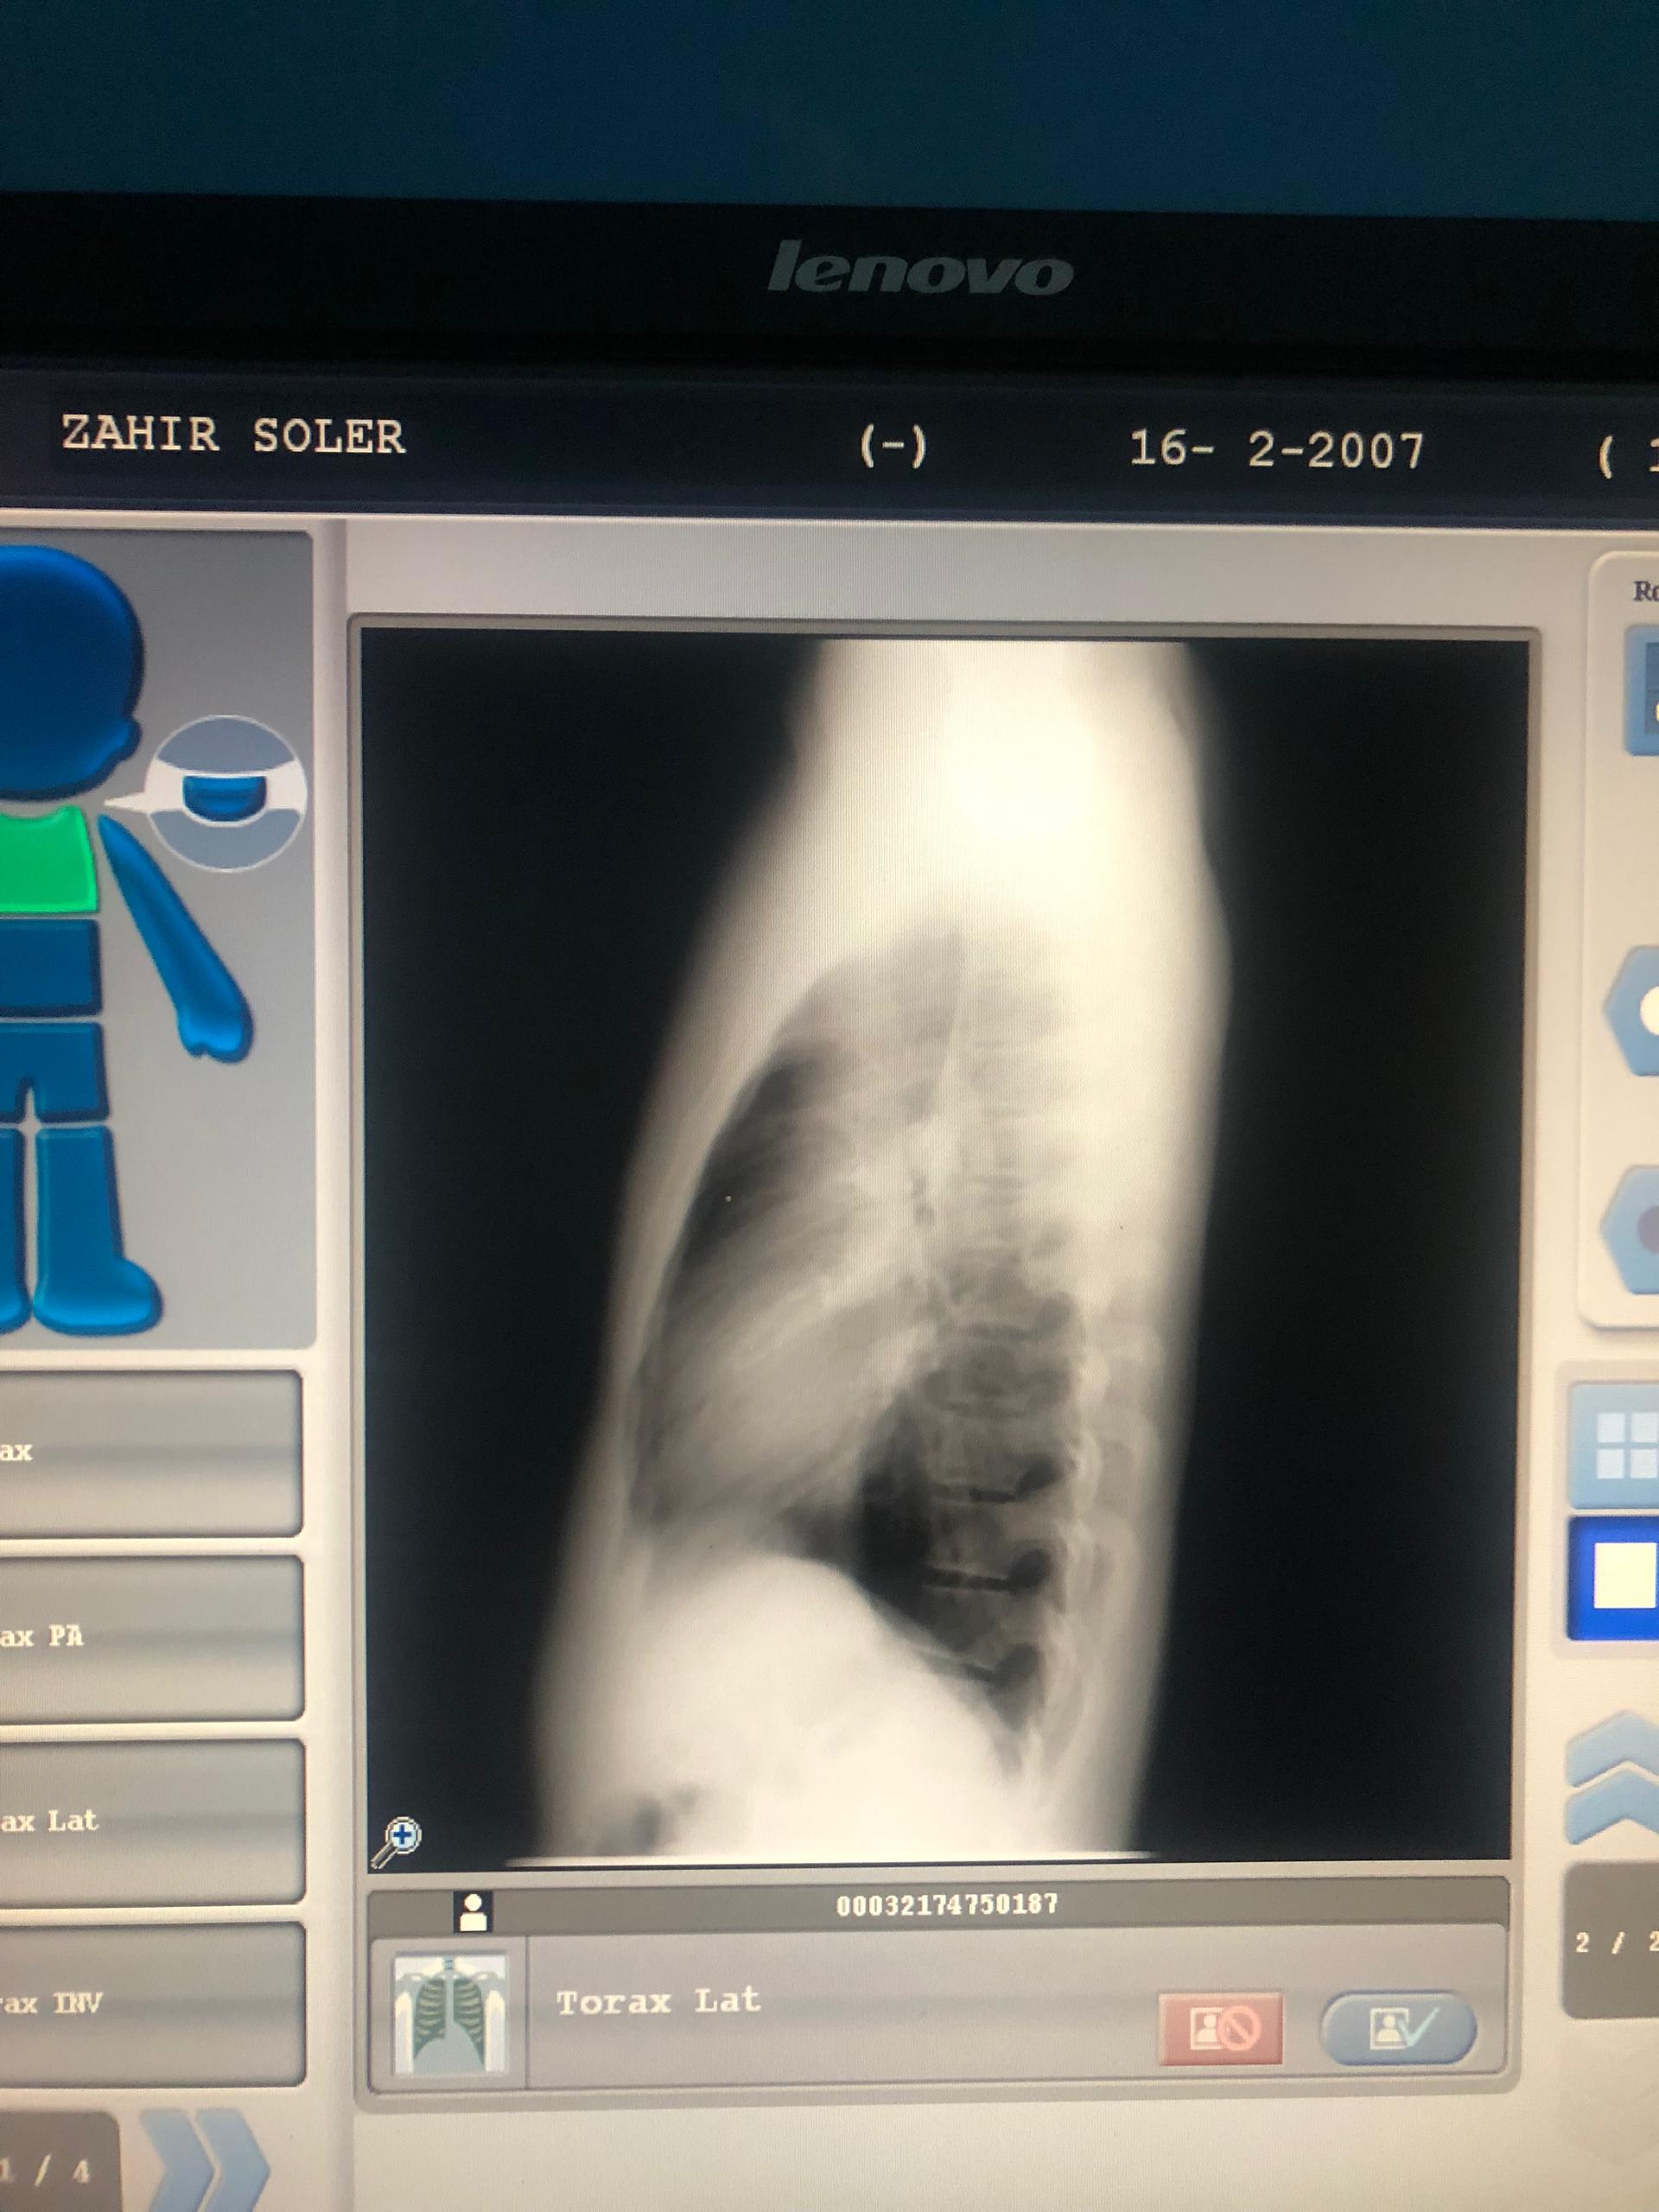

Fue una noche en que no se lo recomiendo a nadie, ni deseo a mi peor enemigo. Esto es una sensación que el simple hecho de toser, toser y no poder respirar es de lo peor. Esa noche me nebulicé para que pudiera entrar oxígeno y calmar la situación; sin embargo, sabía que tenía que ir al doctor para ver qué era lo que tenía. Primero fui al radiólogo, para hacerme una placa de rayos X. La chica, al ver mi placa, me comentó que era un patrón de neumonía que, si no me cuidaba, podría estar al borde de otro posible ataque.

It was a night I wouldn't recommend to anyone, nor wish on my worst enemy. It's a feeling that just coughing, coughing and not being able to breathe is the worst. That night I used a nebuliser so that oxygen could get in and calm the situation down; however, I knew I had to go to the doctor to see what was wrong with me. First I went to the radiologist to have an X-ray. The girl, upon seeing my X-ray, told me that it was a pattern of pneumonia and that if I didn't take care of myself, I could be on the verge of another possible attack.